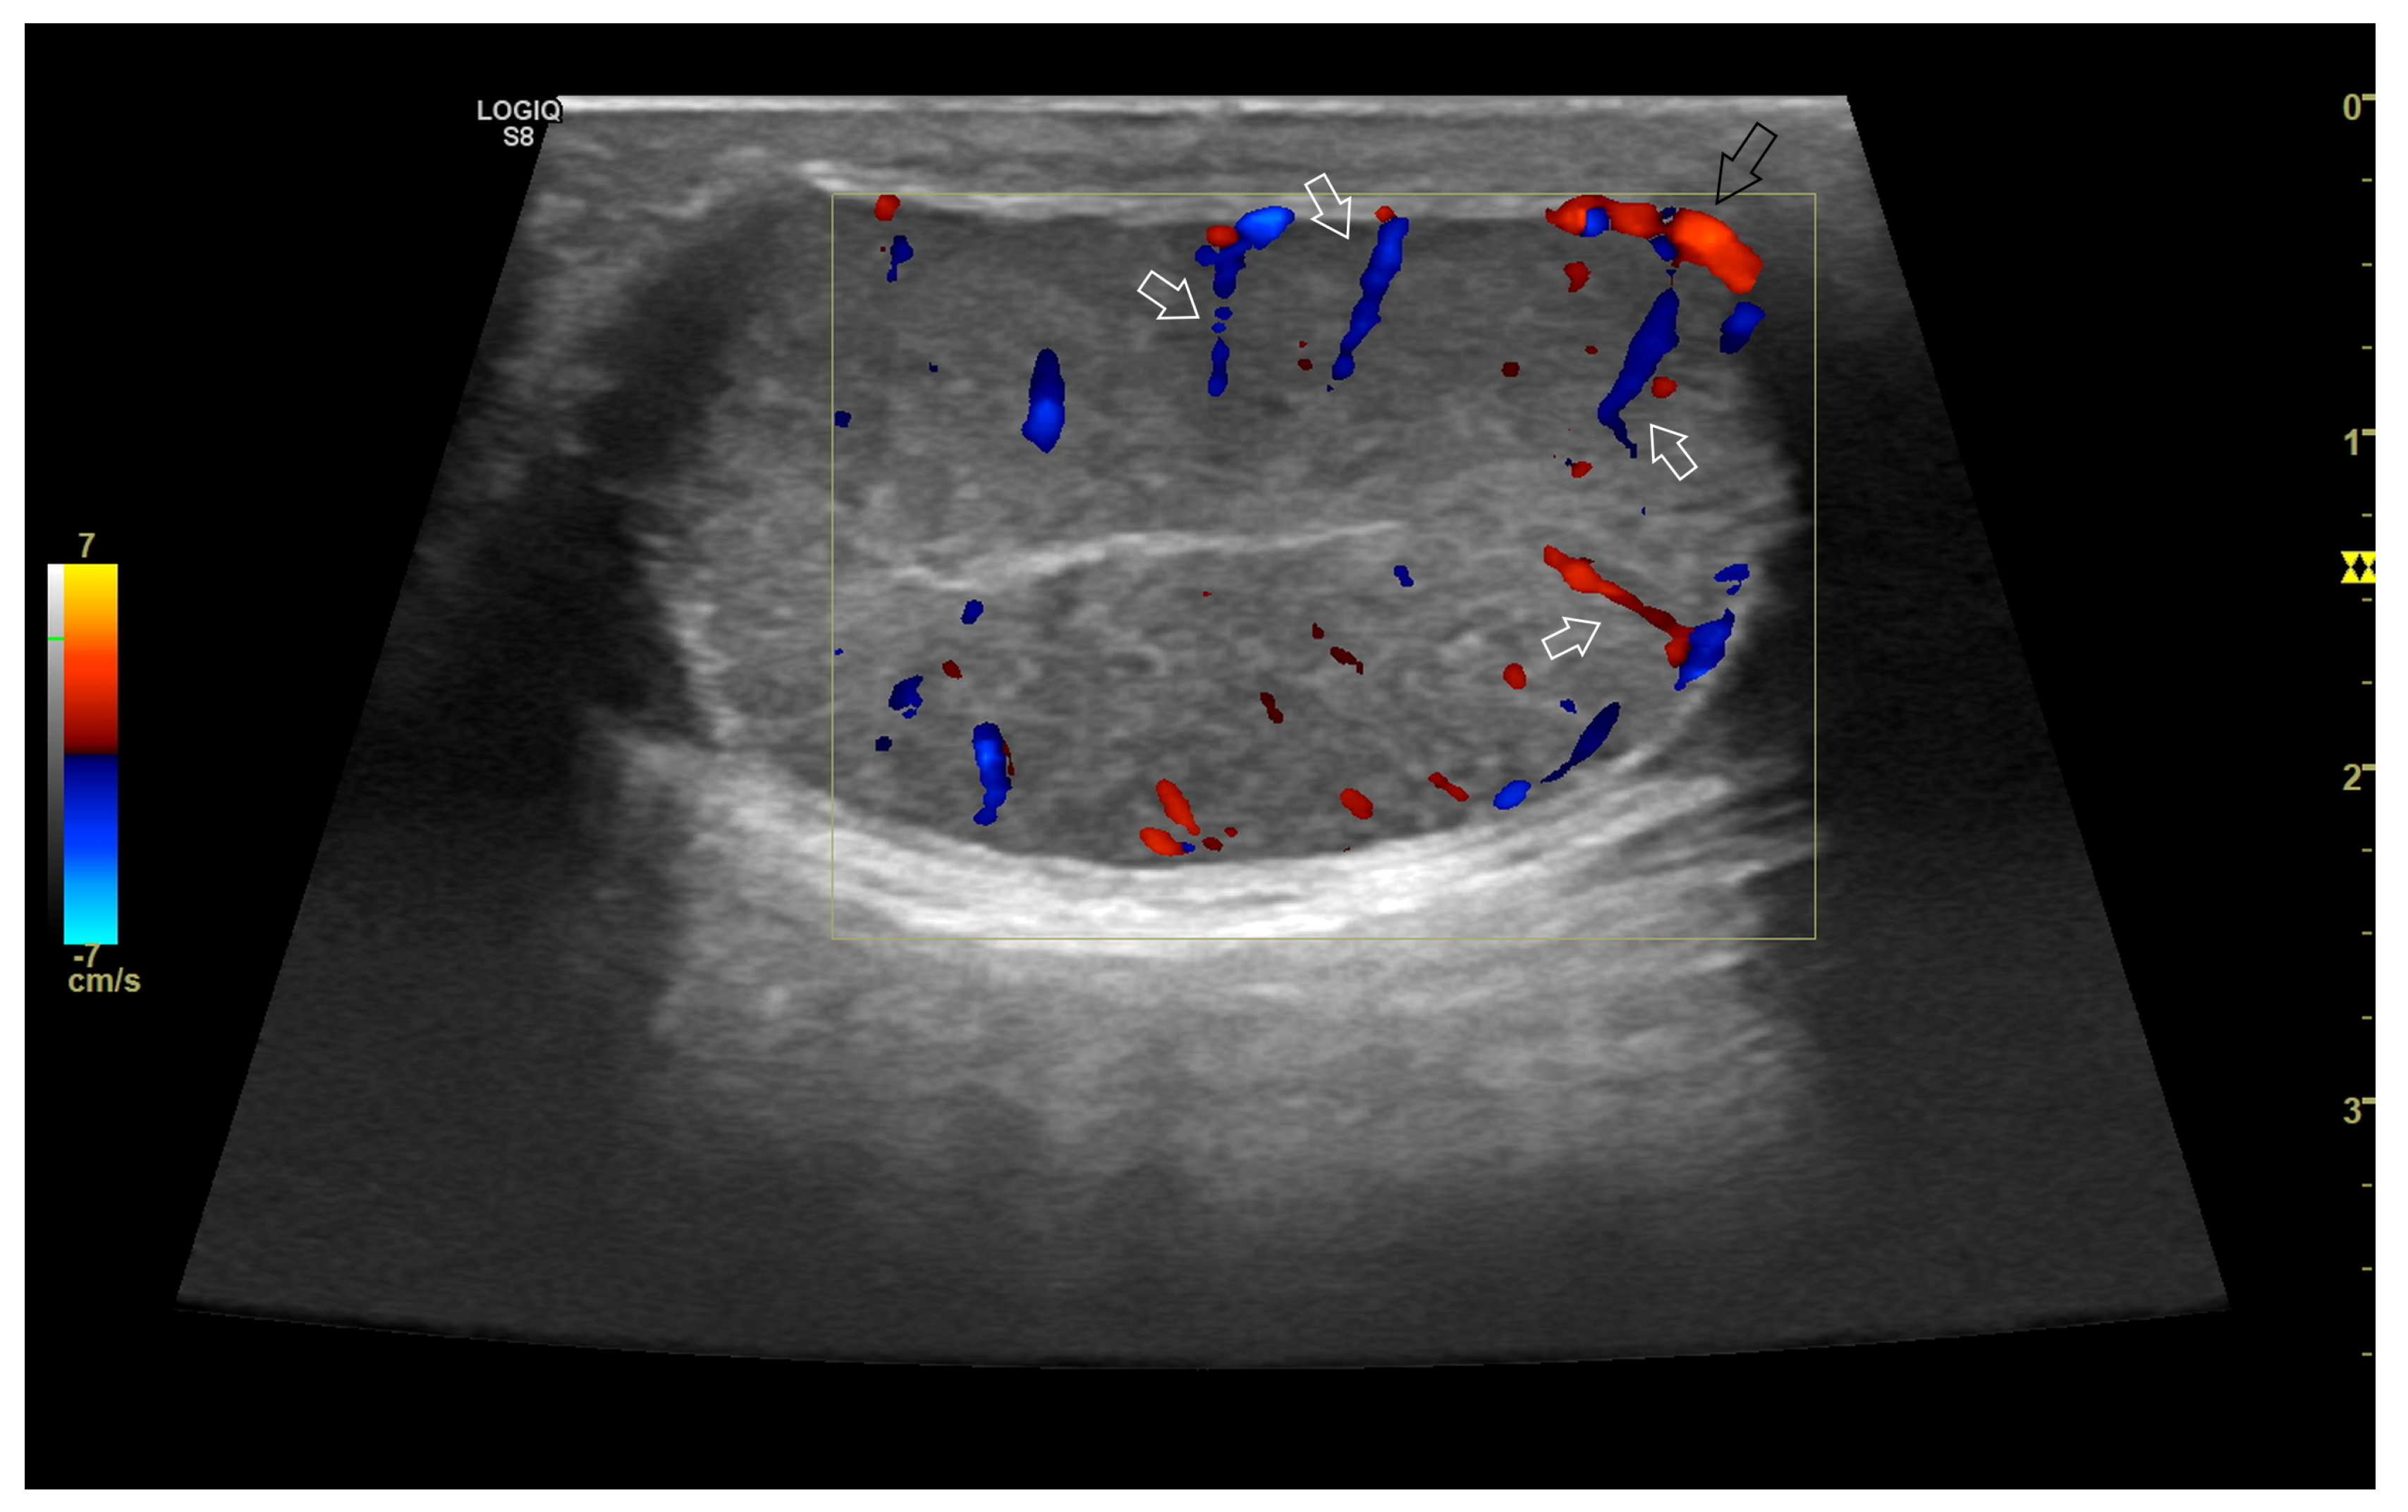

4.3. Relationship between Spectral Doppler Measurement and Dog’s Semen Quality

4.4. Abnormal Findings